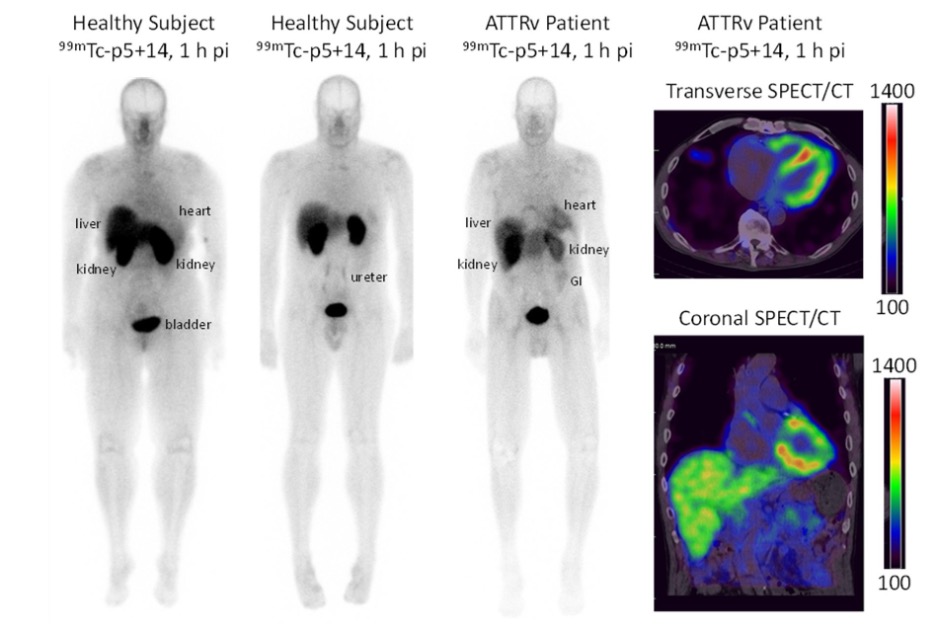

Tumors of the Bones and Joints (AFIP Atlases of Tumor and Non-tumor Pathology, Series 5), Novel Radiotracer Produces High Quality Images of “Alzheimer's Disease of the Heart” | Imaging Technology News,

Novel Radiotracer Produces High Quality Images of “Alzheimer's Disease of the Heart” | Imaging Technology News, Unmasking the Genetics of Early Heart Disease - A Womans Health